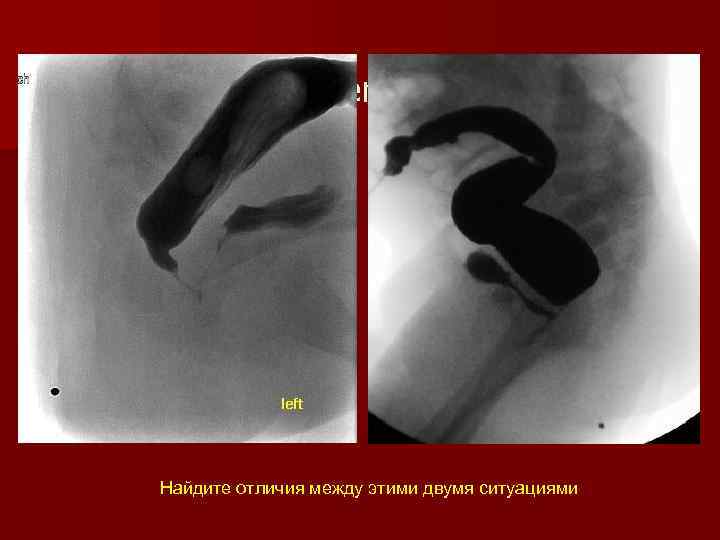

Same level-Different approaches Найдите отличия между этими двумя ситуациями